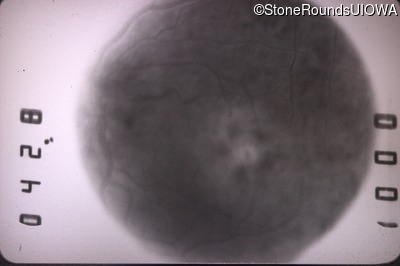

Fluorescein Angiography - Left - 20/400

Exemplar